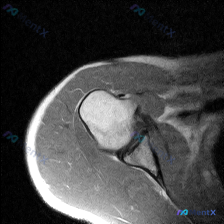

整理了一份肩部MRI影像分析的病例讨论材料。患者具体年龄、性别、完整病史未明确,医生重点关注盂唇病变,但只提供了T1冠状位序列的分析。 现有影像发现: - 肱骨头、肩峰、关节盂形态正常,无骨折/肿瘤迹象 - 冈上肌腱连续,无撕裂、回缩,肌肉无萎缩 - 关节间隙正常,无明显积液/滑膜增厚 - 周围软组...

看到一份肩部MRI(T1序列,冠状位)的病例资料,大家帮忙分析一下。 影像质量:图像信噪比良好,解剖结构清晰。 骨性结构:肱骨头、肩胛骨、肩峰等骨质无明显破坏,关节对位良好。 肩袖结构:冈上肌腱附着处近端区域可见异常信号(肌腱内混杂中等偏高信号),连续性尚存,未见全层中断。 盂唇:下方盂唇结构显示清...

看到一个有意思的肩部病例,主诉提示软组织积液,整理了一下整个分析思路,分享给大家。 病例核心信息 这是一份肩部MRI冠状位T1序列影像,临床关注点为"软组织积液",我们先看影像发现: 1. 骨骼结构:肱骨头上方接近大结节下方,可见境界清晰的地图样不规则低信号区,周围有明显低信号硬化环;肩峰、锁骨、关...